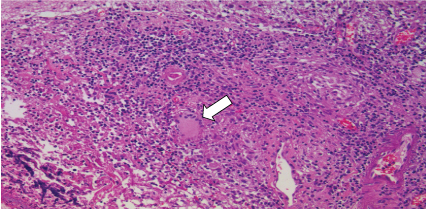

On June 15, 2015, the patient kept his status without clinical improvement, and a new cerebral biopsy was indicated and performed. After one week, the anatomopathological examination of the brain biopsy showed a fungus growth result. This exam indicated a probable diagnosis of histoplasmosis (Figures 2, Figure 3 and Figure 4). Then the neurology service restarted amphotericin B (100 mg per day).

Figure 3: Lymphohistiocytic infiltrate with involvement of the adjacent parenchyma (hematoxylin-eosin increasing by 100x). View Figure 3

Figure 4: Formation of granulomas and multinucleated giant cells near the areas of necrosis, compromising muscularized wall vessels and cerebral parenchyma (hematoxylin-eosin increasing 200x). View Figure 4